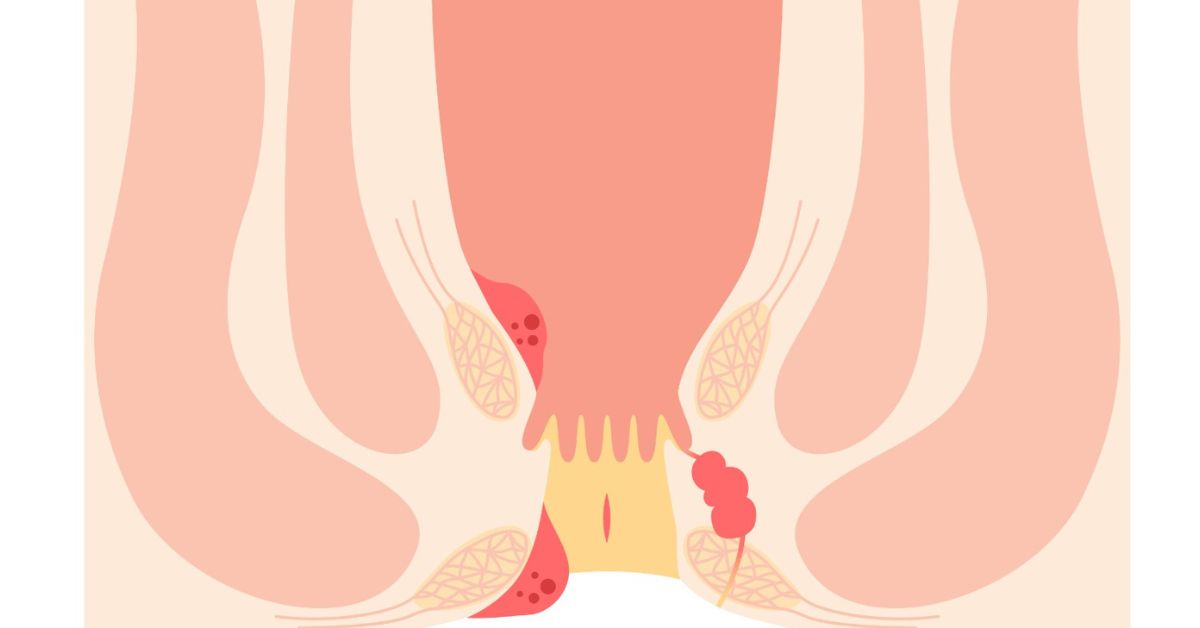

Piles are different in various individuals, but some symptoms are usually observed:

- Itching or burning the anus.

- Bowel pain or post-bowel pain.

- Blood leaves a stain on the tissue.

- A though mass or swelling in the rectum.

- Soreness when sitting in a long sitting.